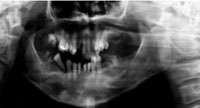

重度の歯周病により、歯を支える骨がほとんど溶けてしまっており、歯がグラグラとなり咬み合わせが大きく崩れている。

数本を抜かずに数年持たせることは出来るが、10年後には崩れたり他のインプラントに悪影響を及ぼす可能性があり、全顎的なインプラント治療をご提案。